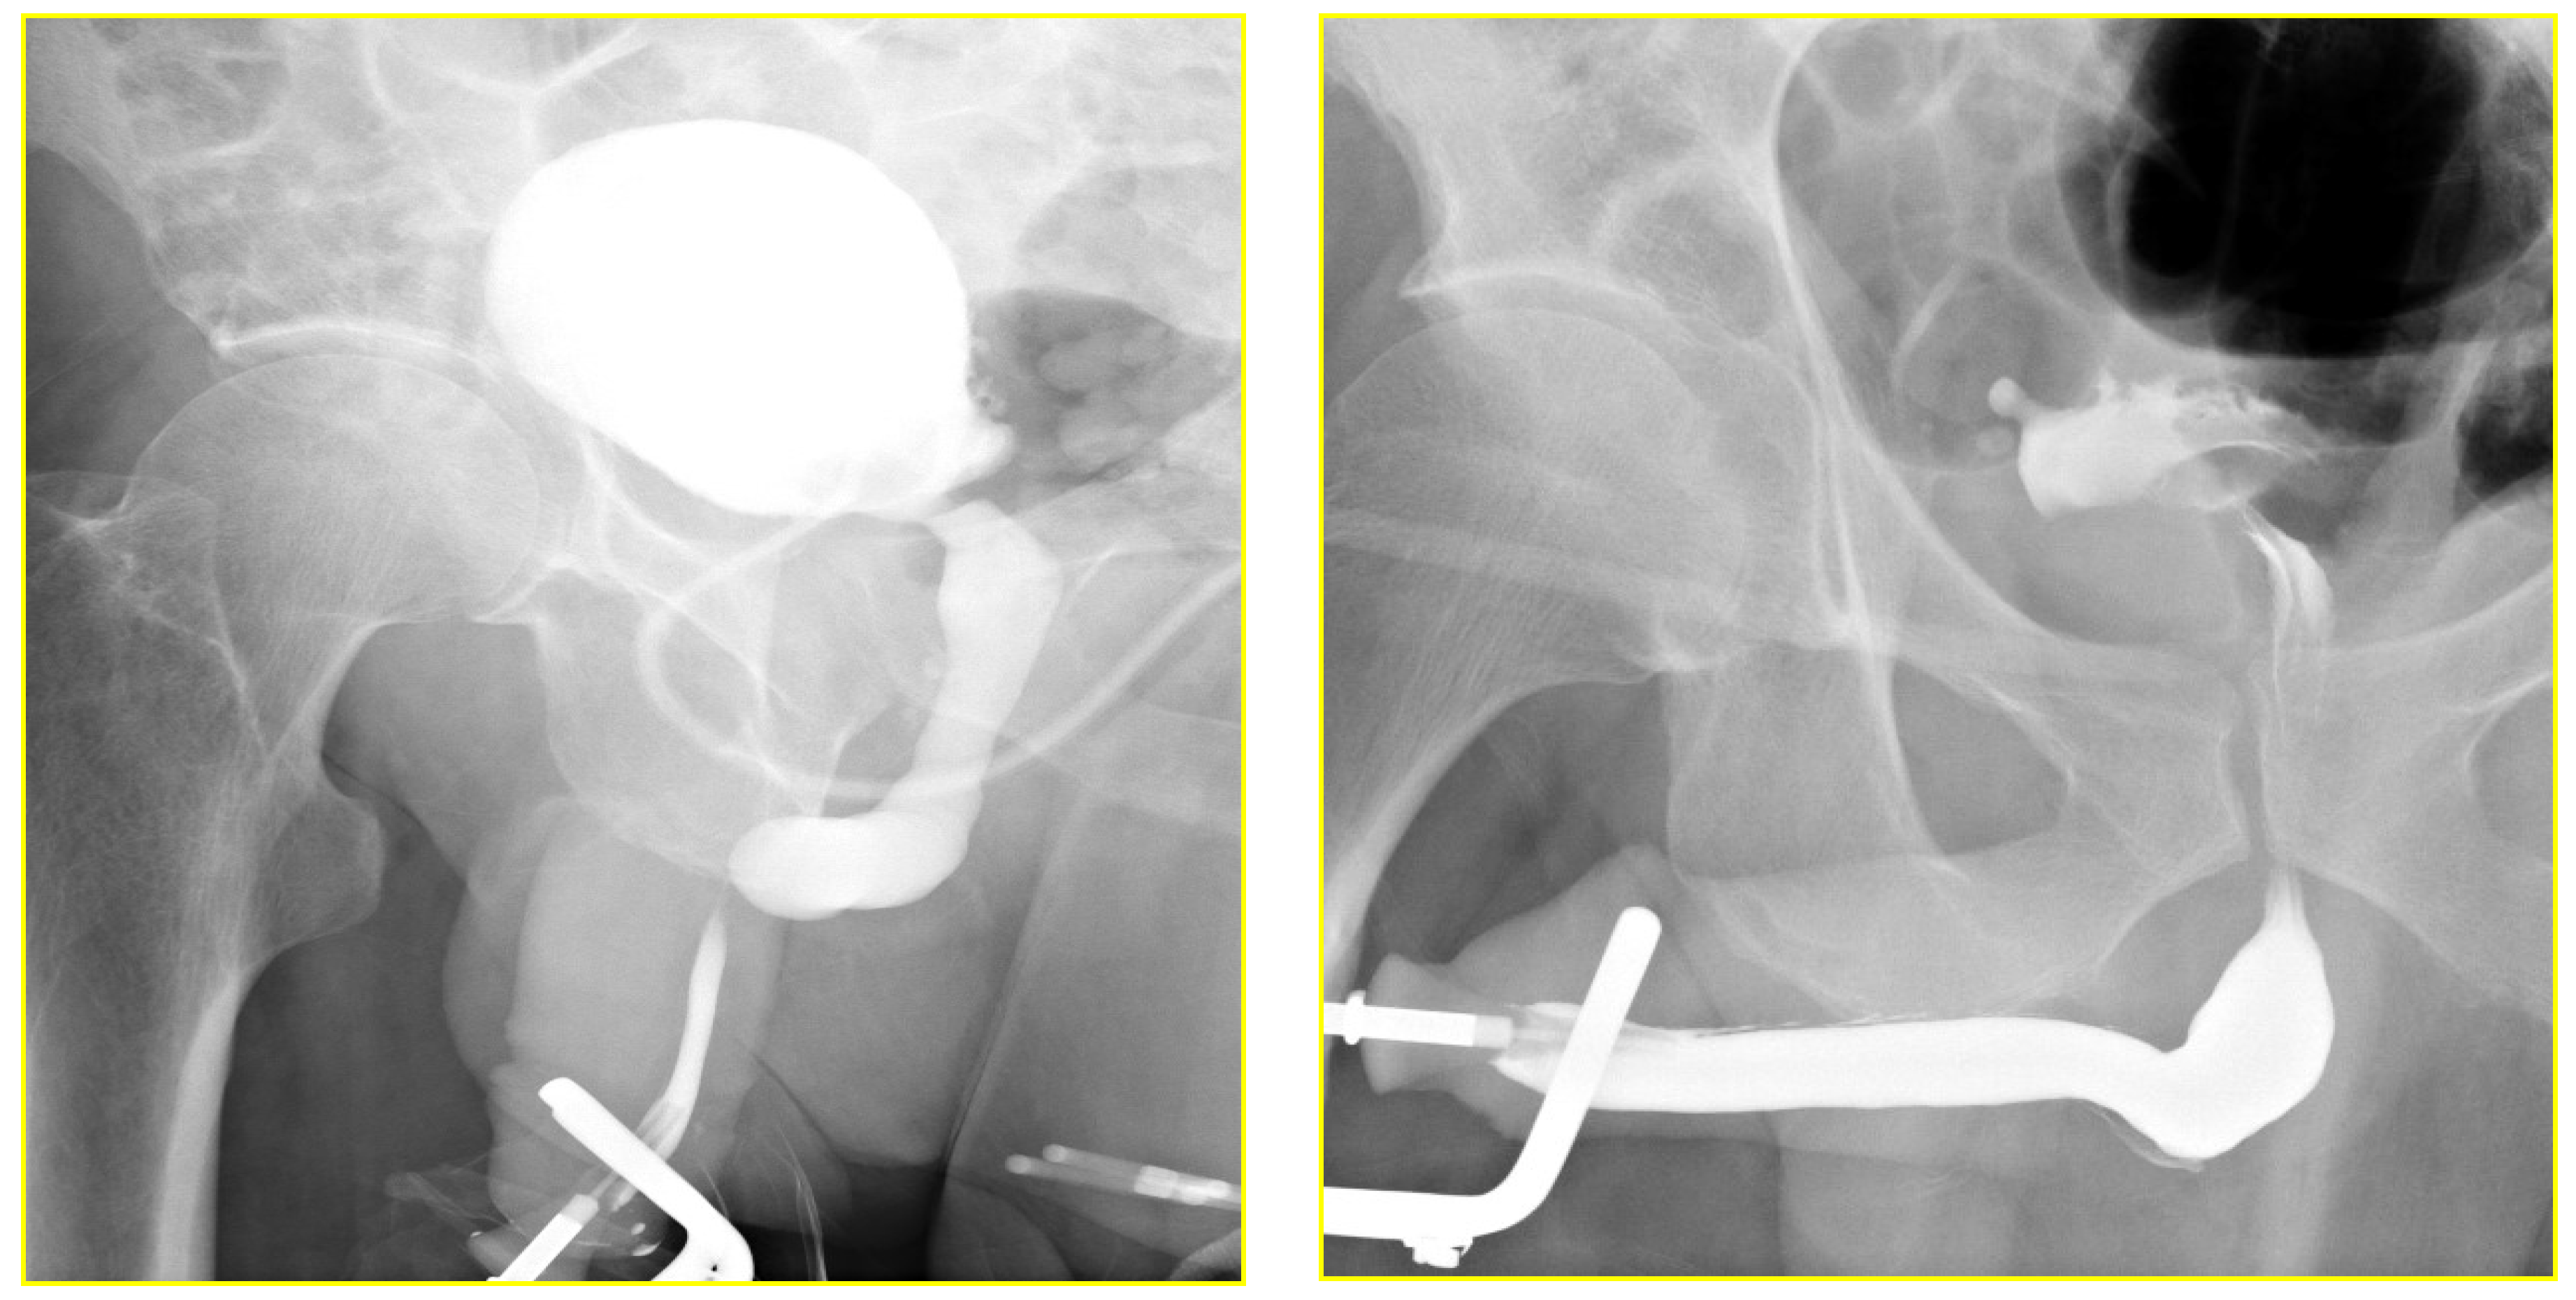

The RGU performed at the time of catheter removal of patients in Group 1 on day one demonstrated minimal extravasation but no voiding difficulty in six patients (32%). These patients were discharged from the hospital without reinserting a Foley catheter. The extravasation cleared up spontaneously when the patients had a follow-up RGU six weeks after catheter removal (Figure 4 and Figure 5). The patients with minimal extravasation did not develop any clinical problems. The patients in Group 2 had their urethral catheters removed two weeks post-surgery, and an RGU was performed six weeks after catheter removal. Stricture recurrence occurred in Group 1 at 3.6 and 6.2 months. The seven failures in Group 2 occurred at an average of 5.6 months (range 1.1 to 10.1) (p = 0.804).

Figure 4. Retrograde urethrogram in a patient with a 2.1 cm stricture pre and 24-h post double-layer running suture re-anastomosis.